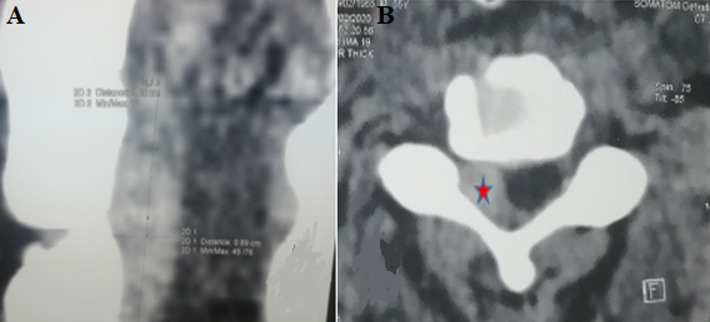

Post-traumatic spinal epidural cervical hematoma is defined as a collection of blood at the level of the epidural space following a trauma. It remains a rare presentation. We report here the case of a cervical epidural hematoma extending from C3 to C5, in a 55-year-old patient victim of a public traffic accident admitted one hour after trauma. Computed Tomography (CT) scan found a compressive epidural hematoma extending C3 to C5; the patient underwent a posterior surgical approach, which allowed to evacuate the hematoma. This rare clinical entity is an emergency diagnosis and management, which needs collaboration between, Intensive Care Unit (ICU) specialists, neurosurgeons, neuroradiologists, and physiotherapists for good outcomes and follow-up.